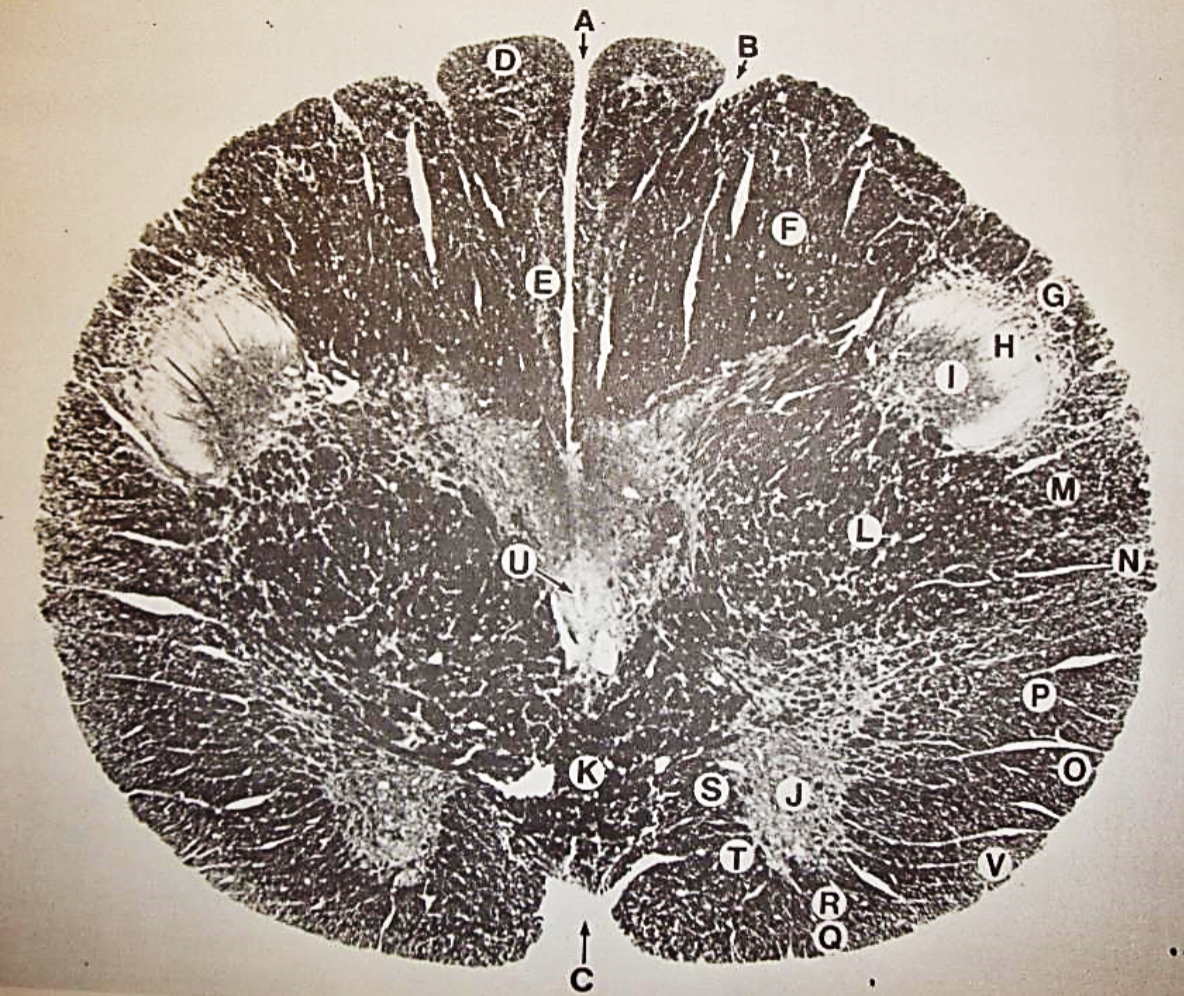

A

Lateral Cuneate nucleus

B

dorsal external arcuate fibers

C + D collectively

vestibular nuclei

C + D collectively

vestibular nuclei

E

dorsal motor nucleus of vagus nerve

F

solitary fasciculus

G

solitary nucleus

H

nucleus ambiguous

I

fascicles of glossopharyngeal nerve

J

hypoglossal nucleus

K

fascicles of hypoglossal nerve

L

dorsal longitudinal fasciculus

M

central tegmental tract

N

inferior olivary nucleus

R

inferior cerebellar peduncle

S

spinal trigeminal tract

T

spinal trigeminal nucleus

U

ventral trigeminothalamic tract

V

pyramidal (corticospinal) tract

W

rubrospinal tract

X

anterior spinocerebellar tract

Y

spinal lemniscus

Z

medial longitudinal fasciculus

a

tectospinal tract

b

medial lemniscus

c

vagus nerve

d

inferior salivatory nucleus